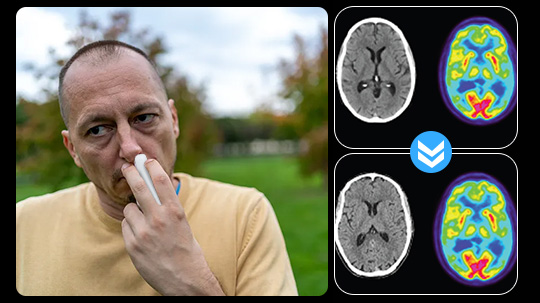

Above: The patient’s PET scan after AlzClipp treatment shows improvement, with cognitive abilities greatly enhanced as the scan approaches that of a normal brain.